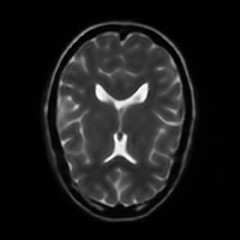

Limited by imaging systems, the reconstruction of Magnetic Resonance Imaging (MRI) images from partial measurement is essential to medical imaging research. Benefiting from the diverse and complementary information of multi-contrast MR images in different imaging modalities, multi-contrast Super-Resolution (SR) reconstruction is promising to yield SR images with higher quality. In the medical scenario, to fully visualize the lesion, radiologists are accustomed to zooming the MR images at arbitrary scales rather than using a fixed scale, as used by most MRI SR methods. In addition, existing multi-contrast MRI SR methods often require a fixed resolution for the reference image, which makes acquiring reference images difficult and imposes limitations on arbitrary scale SR tasks. To address these issues, we proposed an implicit neural representations based dual-arbitrary multi-contrast MRI super-resolution method, called Dual-ArbNet. First, we decouple the resolution of the target and reference images by a feature encoder, enabling the network to input target and reference images at arbitrary scales. Then, an implicit fusion decoder fuses the multi-contrast features and uses an Implicit Decoding Function~(IDF) to obtain the final MRI SR results. Furthermore, we introduce a curriculum learning strategy to train our network, which improves the generalization and performance of our Dual-ArbNet. Extensive experiments in two public MRI datasets demonstrate that our method outperforms state-of-the-art approaches under different scale factors and has great potential in clinical practice.